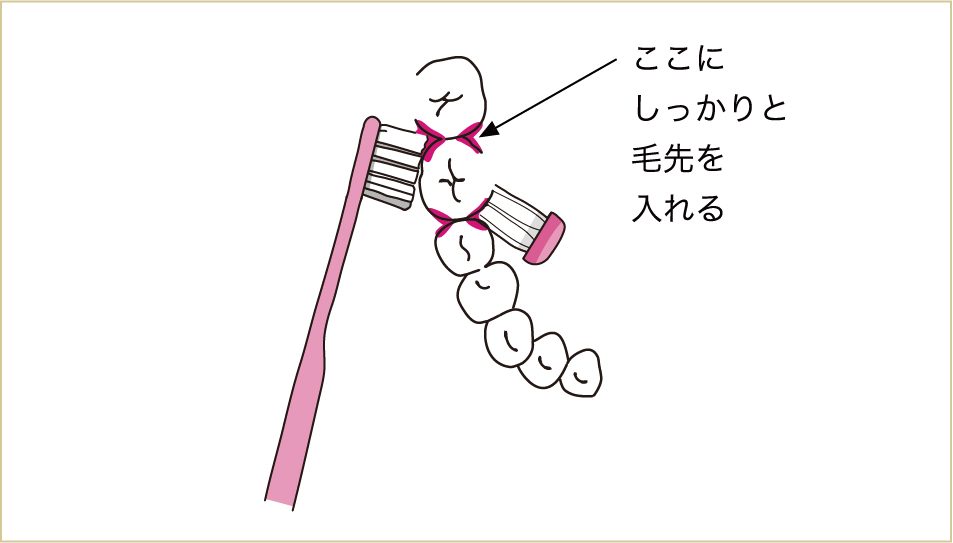

またインプラントは、インプラント同士を2夲、3本と連結することで安定性を向上させていることが多く、ブリッジの手入れと同様、連結部のブラッシングや歯間ブラシ・デンタルフロス(特にスーパーフロスと呼ばれるもの)の使用が大切になります。

ブリッジと同じように、インプラントも連結してある部分を丁寧にしっかりとみがく。

インプラントとインプラントの連結部分、インプラントと歯の間に、しっかりデンタルフロスなどを通す習慣を身につける。

インプラントの連結部はワンタフトブラシなどで良くみがく。歯医者で歯科衛生士に、特殊なブラシの使い方をしっかりと教わることも重要なポイント。

インプラントの連結部やブリッジの下をきれいにするにはスーパーフロスが適している。これは歯科医院でないと入手しにくいので、歯医者さんに問い合わせてみよう。

太線の部分をしっかりとみがいて清潔に保つことが、インプラントを長く使うポイントになる。

奥歯は、矢印のようにスーパーフロスを用いて汚れを拭きあげるイメージを持つ。